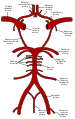

يتم تزويد المخ بالدم عن طريق 4 شرايين هي الشريانان السباتيان الغائران والشريانان الفِقريان[3]. لا يتفرع الشريان السباتي الغائر حتى يدخل الجمجمة من خلال النفق السباتي أسفل الجمجمة. بعد دخول الجمجمة يسير الشريان السباتي على شكل حرف S إلى جانب السرج التركي (باللاتينية: Sella turcica) مروراً بالجيب الكهفي (باللاتينية: Sinus cavernosus) لينقسم إلى فروعه الرئيسية:

- الشريان العيني (باللاتينية: Arteria ophthalmica) والذي يزوِّد العين بالدم.

- الشريان المخّي الأمامي (باللاتينية: Arteria cerebri anterior) والذي يزود الجزء الأمامي للدماغ بالدم.

- الشريان الموصِّل الخلفي المُخِّي وهو جزء من الدائرة الشِّريانية الدِّماغية (باللاتينية: Cirulus arteriosus).

ثم يتغير أسم الشريان السباتي الغائر ليشكل الشِّرْيانُ المُخِّيُّ الأَوسَط، هذا الشريان الذي يعتبر امتداداً للشريان السباتي الغائر، والذي يزود الجزئين الجانبيين من الدماغ.